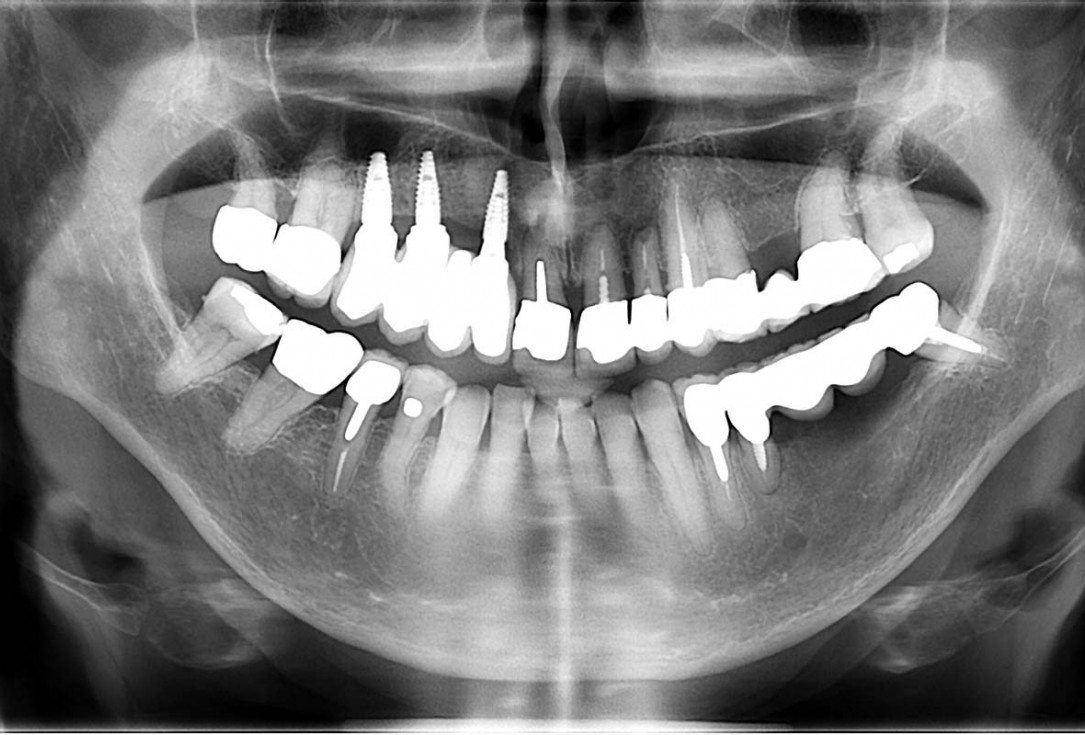

Ridge augmentation in the maxilla with maxgraft® bonebuilder in the aesthetic zone - Dr. M. Kristensen

Bone defect in area 11-21 due to two lost implants (periimplantitis) after 15 years of function